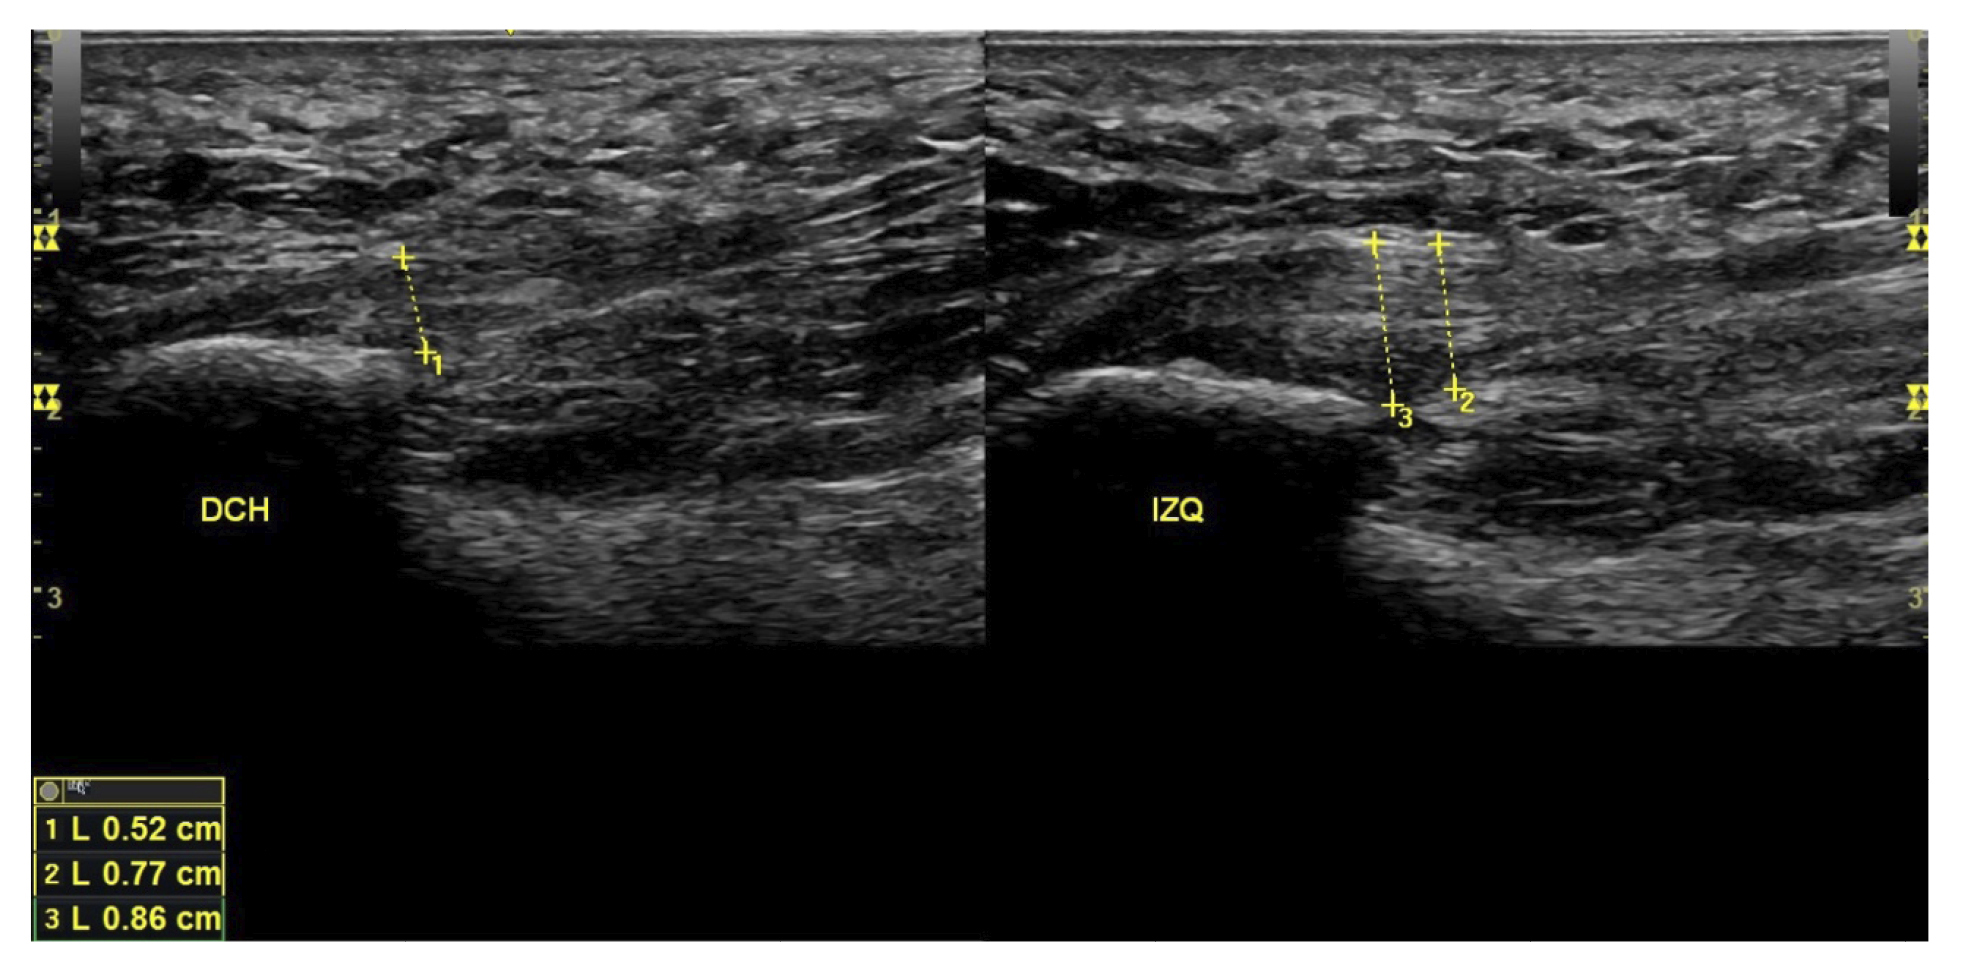

All patients underwent a clinical evaluation and an ultrasound evaluation. The clinical evaluation was based on a visual analog scale (VAS) (13) (0-10) and the Foot Function Index (FFI) (14,15), which assesses function on a scale of 0 to 100. Subjects were also classified as sedentary, active, or athletes based on their daily physical activity, as well as whether it was the first time the disease appeared, a recurrence, or chronic(16). Sex, weight, and height were also evaluated, as well as the presence of vascularization in the plantar fascia visualized with ultrasound at the time of the initial evaluation and the biconvex17 or flattened shape of the plantar fascia (Figure 1).

Figure 1. Plantar fascia with normal morphology on the left and biconvex plantar fascia on the right.